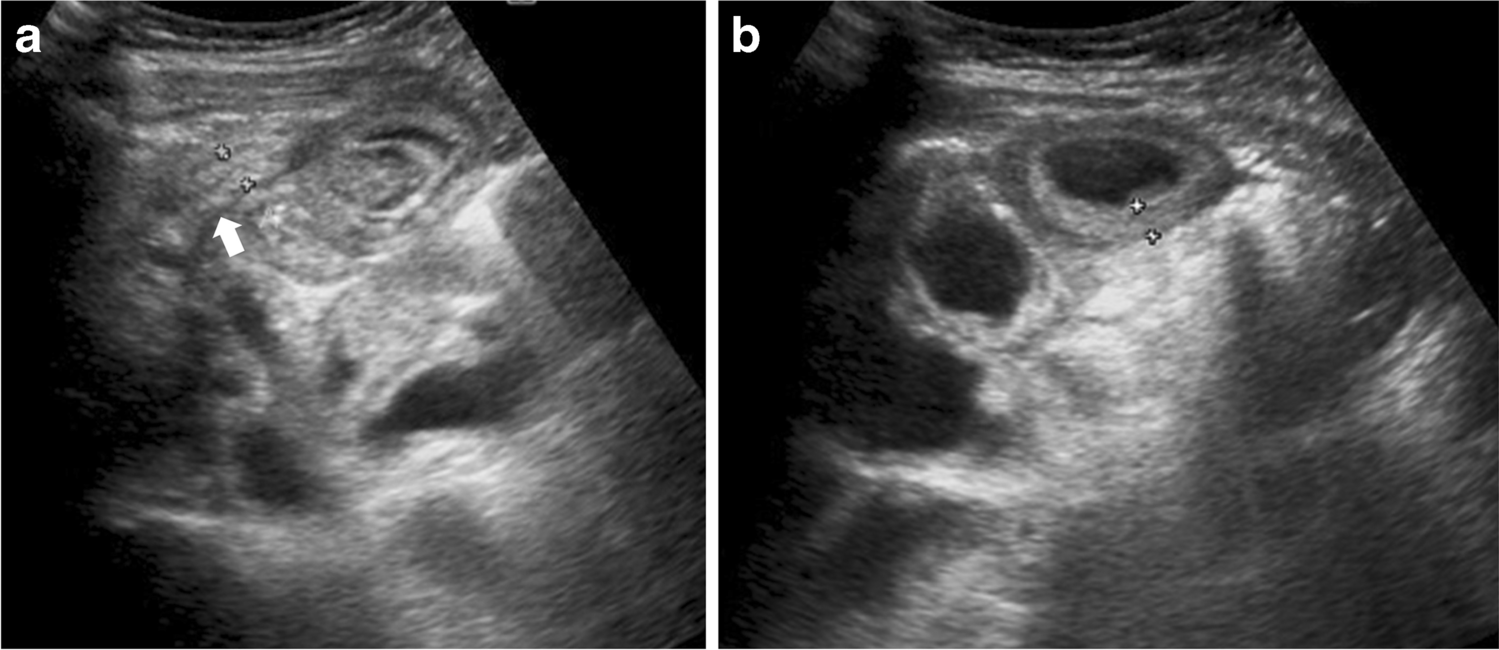

Fig. 1

Case 1: US abdomen in a 6-year-old girl who presented with back and right iliac fossa pain. a, b Transverse US section of the right iliac fossa. The appendix (white arrow in a) appears inflamed with a diameter of 6 mm. Note inflamed mesentery, enlarged mesenteric lymph nodes (black arrow), thickened distal ileum (*) and cecum (white arow in b), with free fluid in both paracolic gutters (not shown)

The most common imaging finding in our study was the presence of free fluid, mesenteric inflammation and mesenteric lymphadenopathy (Figs. 1, 2, 3 and 4). We noted that the abnormal nodes were quite prominent, with an average short-axis size of 11.9 mm and average long-axis size of 19.1 mm. Half the children with lymphadenopathy (6/12) had more than six enlarged mesenteric lymph nodes. It is possible that the particularly prominent size of nodes is a phenomenon of PIMS-TS, noting that multiple large lymph nodes are not generally seen in acute appendicitis. Such enlarged lymph nodes can be seen in inflammatory bowel disease (IBD), which generally has small bowel wall asymmetrical thickening (along the mesenteric border), segmental mural enhancement and mesenteric fat expansion [27, 28]; however, the advanced cases of IBD are usually associated with small-bowel stricture, ulcerations and sacculation, fistulas and abscess formation [29].

Abnormal bowel thickening predominantly involving the distal ileum and cecum was observed in a third (35%) of our cases, with an average bowel wall thickness of 5 mm (range 4–7 mm) (Figs. 1 and 4). Some cases also had jejunal (3/23), sigmoid (1/23) and distal esophageal (1/23) involvement. Bowel thickening (especially long-segment ileal involvement) is thought to be much more specific for PIMS-TS and is uncommon in other potential mimics such as acute appendicitis (bowel thickening if present is usually limited to terminal ileum and cecal pole), infective enteritis (asymmetrical thickening of the ileocecal valve, cecum and terminal ileum and enlarged necrotic ileocolic lymph nodes for tuberculous enteritis or symmetrical wall thickening of terminal ileum and most of the colon without involving the surrounding mesenteric fat in acute bacterial enterocolitis) or mesenteric adenitis (surrounding fat-stranding and absence of an underlying cause) [3032]. A bioinformatics analysis has revealed that angiotensin-converting enzyme 2 (ACE2) receptor expression is significantly higher in the esophagus, ileum and colon [33]. SARS-CoV-2 has a special affinity for ACE2 receptors, and to some extent this explains the propensity for involvement of ileum and colon [34] in our cases.

Another important observation in our study is evidence of appendiceal involvement in 7/23 (30%) cases, which is contrary to the current literature on PIMS-TS (Figs. 1, 2, 3 and 4). In a routine clinical setting, acute appendicitis (enlarged appendix ≥6 mm) is commonly associated with peri-appendiceal fat-stranding, focal cecal apical thickening (arrowhead sign), adenopathy, fluid in right paracolic gutter or appendicolith [27]. In our study, all cases with appendiceal thickening also had distal ileum (not limited to ileo-cecal junction) and cecum (circumferential wall thickening extending to involve the ascending colon in some cases) involvement, in addition to mesenteric inflammation, lymphadenopathy, and free fluid (Fig. 4).